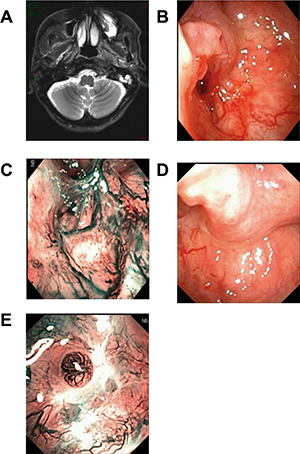

Figure 1: Patients with first diagnosed NPC. Head and Neck MRI (T2WI + contrast) scan showed the slightly blunt fossa of Rosenmuller, local bulging mucosa and slightly high signal swollen medial pterygoid and longus capitis on the left side (A). Under WL, part of the torus tubarius was missing by forceps biopsy (B). Under NBI, mucosa in biopsy area was hyperemia, there was no positive found as brownish spots (C). The CNB puncture point with distance and closer view 2 weeks later, under WL and NBI respectively (D and E).

All the nonexophytic nasopharyngeal lesion patients were first examined with white light (WL) endoscope and then NBI. Some patients present an abnormal swelling, but the overlying mucosa appeared otherwise normal. For the 5 cases of primary NE-NPC patients, lymphoid tissues were observed in nasopharyngeal area under WL (Figure 1B), and the lymphoid tissues appeared imbricate arrangement under NBI. For the 7 cases of recurrent NE-NPC patients, due to radiotherapy, local mucosa and lymphoid tissue were atrophy. Local eminence with smooth surface was observed in back/lateral wall of nasopharynx under WL (Figure 1B, 2B). Under NBI, typical abnormal vessels were not found in any cases (Figure 1C, 2C), which indicate all of them are not mucosal NPC.

To be noted, CNB is not suitable for suspected vascular or cystic lesions and the enlarged retropharyngeal lymph node, because the procedure would cause bleeding and infections under these situations. The lateral cutting groove of the 18G auto-biopsy gun is 1cm. So, tumor diameter more than 1cm is an indication of CNB. Tumor seeding along the needle track after CNB of a lump in the head and neck cancer is 0.0011%, [18] thus, the chance for needle-path tumor implantation in NE-NPC should be low. The puncture point and the needle-path are all in the region of the following radiation or operation (Figure 1D, 1E, 2D, 2E). There were no patients had recurrent tumor at the puncture point in our study during the follow-up time.